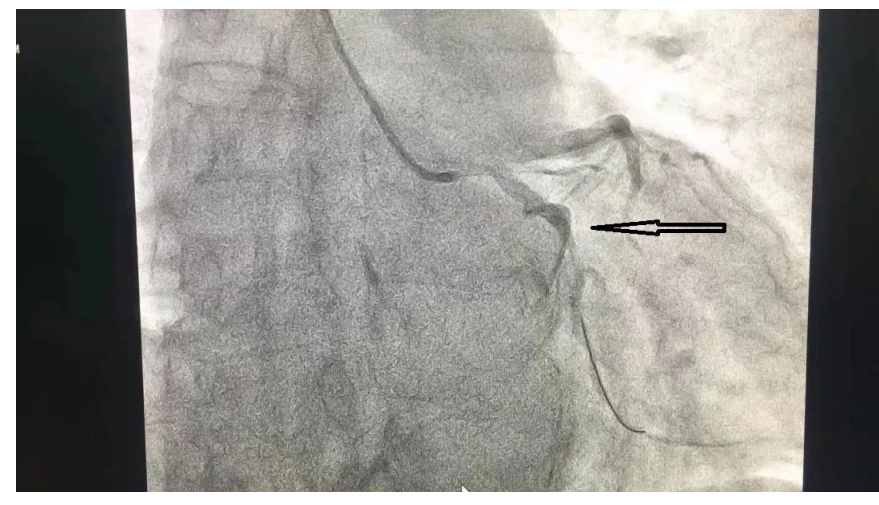

2月11日,63岁的王大爷因“急性胸痛”就诊,急诊科迅速诊断为“急性高侧壁、正后壁心肌梗死”。“时间就是生命,时间就是心肌”,此刻的每一分钟都是在和死神争夺,与时间赛跑,与生命抗衡!面对危重情况,我院立即启动绿色通道,心血管内科副主任医师郑全、主治医师龙泉杉为患者紧急进行“冠脉造影术”,发现回旋支近段完全闭塞,决定为患者行冠脉介入治疗。

术中,先送入球囊扩张闭塞的回旋支,再冠脉内给予普佑克20mg(溶栓药)溶栓,闭塞的血管开通,血流完全恢复。把患者成功从死亡线上拉了回来。

溶栓前